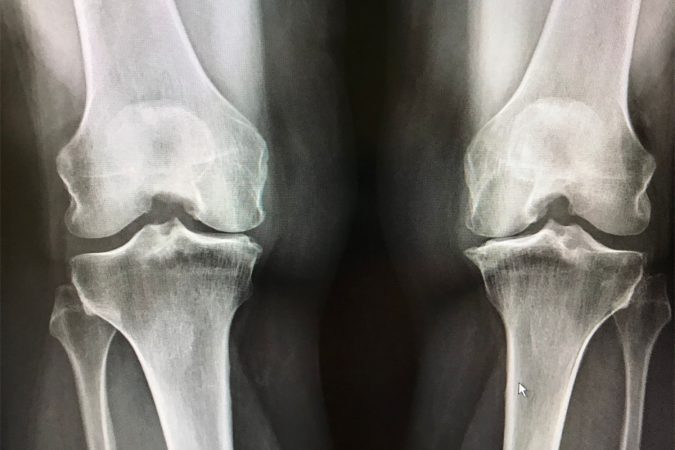

Osteoarthritis is the most extensive type of arthritis, affecting millions of people across the globe. It transpires when the preventive cartilage that pads the ends of the bones becomes worn over time. Despite the fact that osteoarthritis can be damaging to any joint, the disease most commonly affects joints in the knees, hands, hips, and…